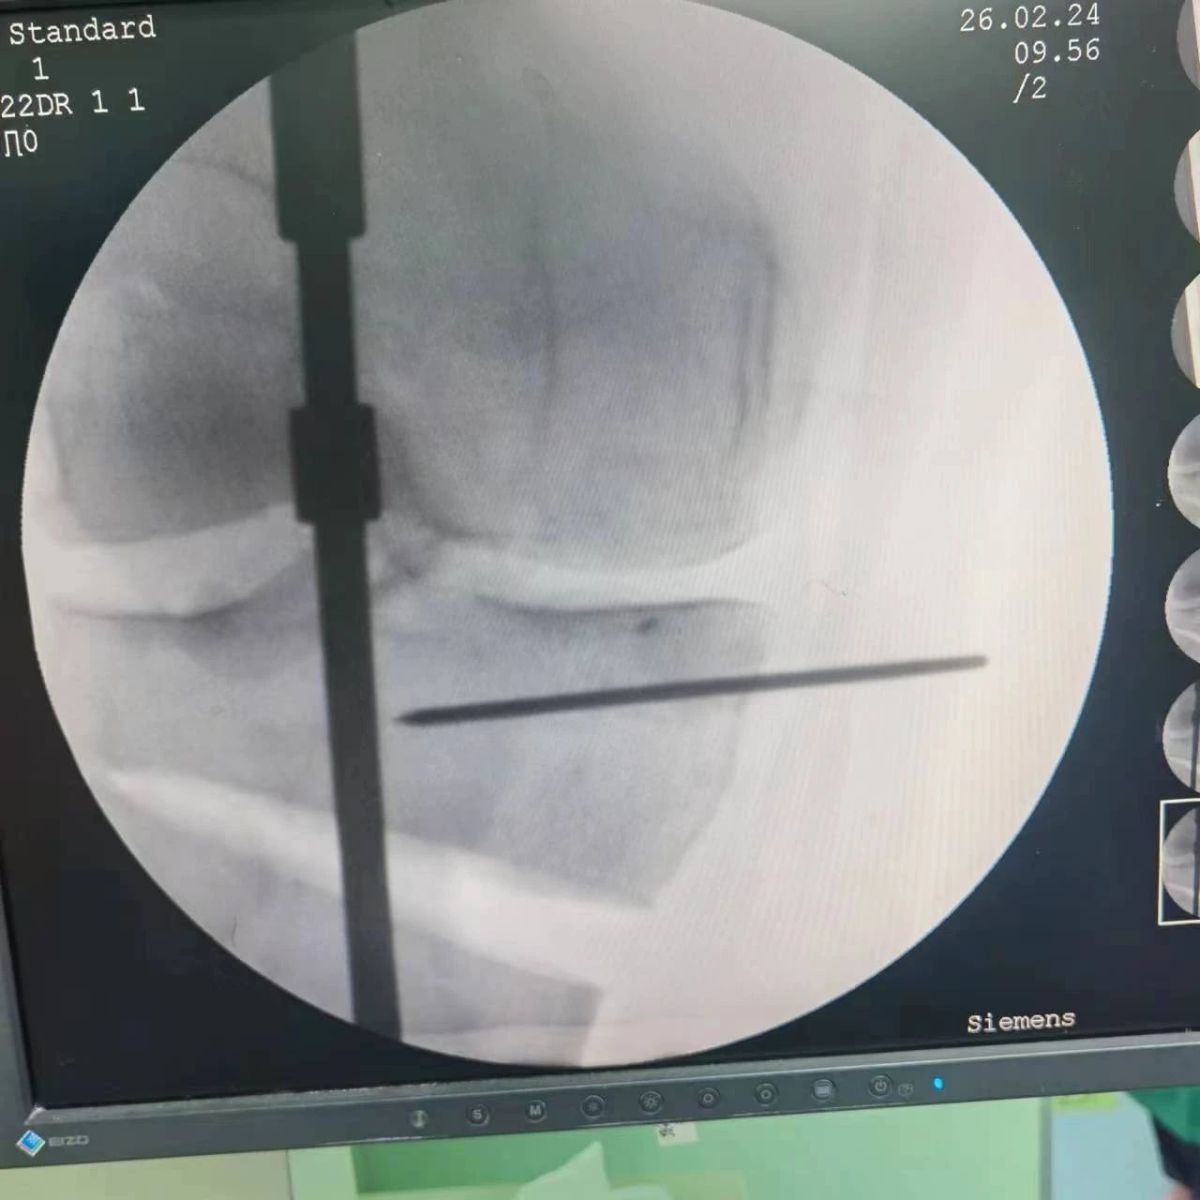

2月26日,漯河市骨科醫(yī)院(漯河醫(yī)專(zhuān)二附院、漯河市立醫(yī)院)膝關(guān)節(jié)外科、運(yùn)動(dòng)損傷科(骨六科)在保膝治療方面取得了新的突破,李付彬主任帶領(lǐng)岳龍等團(tuán)隊(duì)醫(yī)師,順利完成“計(jì)算機(jī)精準(zhǔn)術(shù)前規(guī)劃聯(lián)合3D打印截骨導(dǎo)板輔助脛骨高位截骨治療膝關(guān)節(jié)骨性關(guān)節(jié)炎”的手術(shù),這在漯河市尚屬首例!

李付彬主任團(tuán)隊(duì)通過(guò)精準(zhǔn)術(shù)前規(guī)劃,設(shè)計(jì)目標(biāo)力線(xiàn)及調(diào)整撐開(kāi)角度,轉(zhuǎn)化成需要撐開(kāi)的高度,最終設(shè)計(jì)出同等高度的填充塊,術(shù)中驗(yàn)證力線(xiàn)調(diào)整與術(shù)前規(guī)劃完全一致!

鋼板位置、螺釘位置及長(zhǎng)度均可通過(guò)術(shù)前規(guī)劃計(jì)算,術(shù)中通過(guò)定位操作,基本與術(shù)前規(guī)劃一致,手術(shù)快速高效完成,外側(cè)合頁(yè)保留完整。無(wú)任何并發(fā)癥出現(xiàn)。術(shù)后見(jiàn)鋼板位置及力線(xiàn)糾正近乎完美!